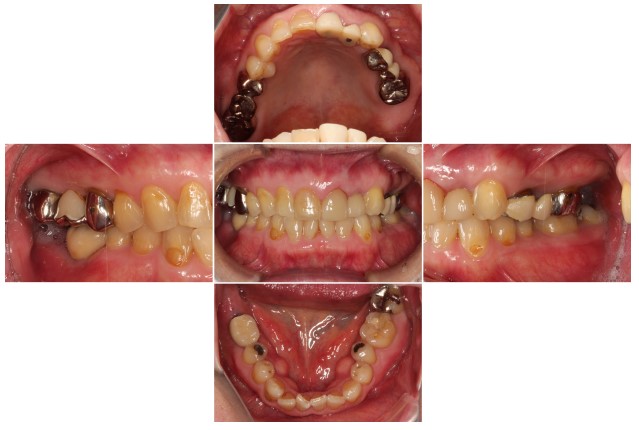

2024.08.1750代女性「歯科恐怖症で治療ができなかった。歯がボロボロで噛めない」インプラントとメタルボンドを入れ、物が噛めてご飯が食べられるようになった症例